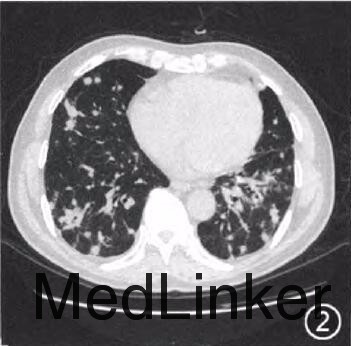

查体:未查见特殊 辅查:单核细胞百分比0.15(参考值0.03~0.13),c反应蛋白13.9mg/L(参考值<7.9mg/L),甲胎蛋白、癌胚抗原、CAl25、CAl99、CA153阴性,真菌-D-葡聚糖:97ng/L(参考值<80ng/L),曲霉菌半乳甘露聚糖0.19(参考值<0.50),自身抗体谱:抗内皮细胞抗体(+),抗核抗体、抗ENA抗体、抗线粒体抗体阴性。胸片示(图1):双肺野弥漫多发团片状、结节状高密度影,边界不清,双下肺为著。胸部CT提示(图2,3):双肺野弥漫多发团片状、结节状及索条状高密度影,大部分边界不清,以双下肺为著,部分结节内可见小空泡;纵隔多发大小不等淋巴结影,较大者约2.3cm×l.3cm。行肺内结节穿刺活检,病理检查:镜下见肺组织纤维化,淋巴、浆细胞浸润,可见多核巨细胞及坏死,符合肉芽肿性炎症性病变(图4)。免疫组织化学染色结果:PAS染色(-),抗酸染色(-)。活检组织块真菌培养阳性,六胺银染色检见孢子,病理见大量化生的纤毛柱状上皮细胞、大量炎细胞及坏死碎屑,未见恶性肿瘤细胞。